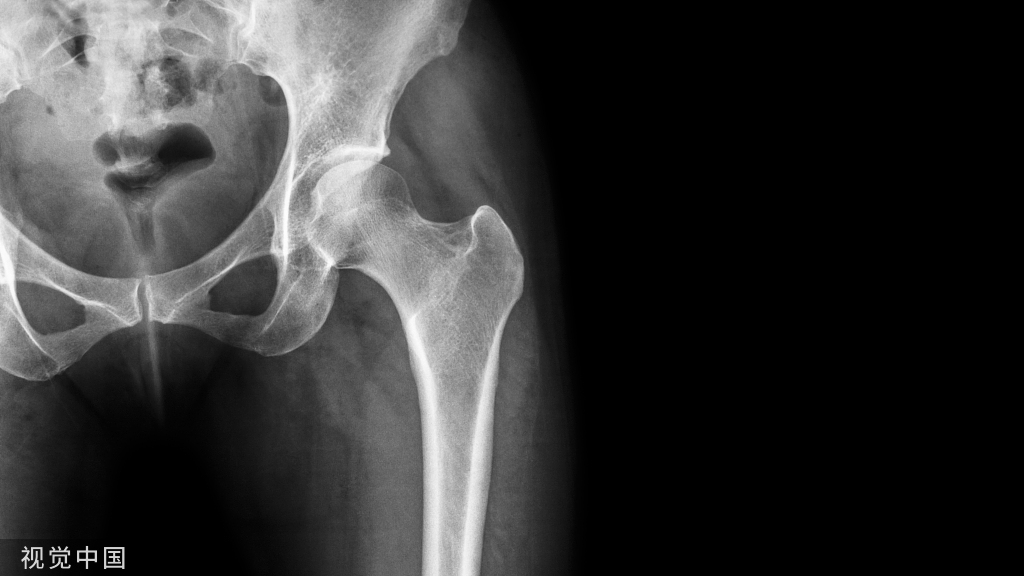

这样一个粗隆间骨折,骨折线经过入钉点,这个时候复位比较困难,及时复位,进钉的时候也很容易将骨折线撑开而造成复位不良。